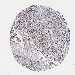

UROTHELIAL CANCER - Protein expressioni

A mouse-over function shows sample information and annotation data. Click on an image to view it in a full screen mode. Samples can be filtered based on level of antibody staining by selecting one or several of the following categories: high, medium, low and not detected. The assay and annotation is described here.

Note that samples used for immunohistochemistry by the Human Protein Atlas do not correspond to samples in the TCGA dataset.

Antibody stainingi

Antibody staining in the annotated cell types in the current human tissue is reported as not detected, low, medium, or high, based on conventional immunohistochemistry profiling in selected tissues. This score is based on the combination of the staining intensity and fraction of stained cells.

Each image is clickable and will lead to virtual microscopy that enables deeper exploration of all samples and also displays staining intensity scores, fraction scores and subcellular localization as well as patient and tissue information for each sample.

Antibody HPA043160

Staining

High

Medium

Low

Not detected

Intensity

Strong

Moderate

Weak

Negative

Quantity

>75%

75%-25%

<25%

None

Location

Nuclear

Cytoplasmic/membranous

Cytoplasmic/membranous,nuclear

Urothelial carcinoma, High grade